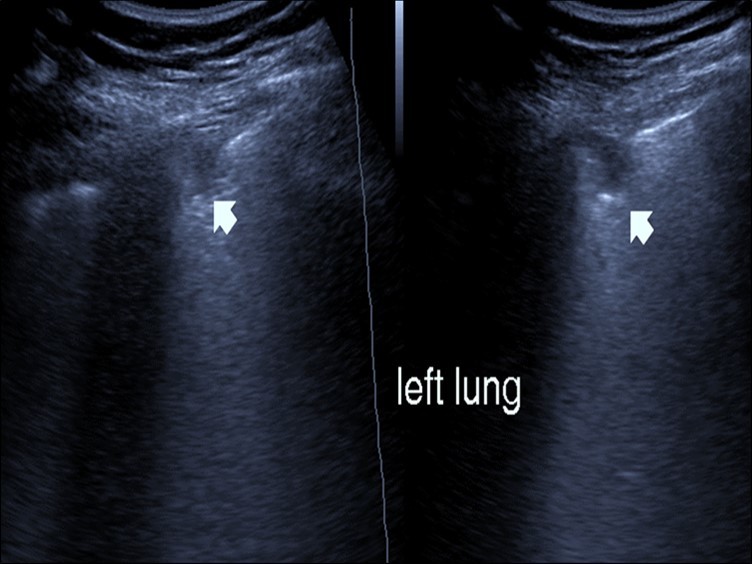

Bed side chest ultrasound may reveal positive findings as multiple Kerley’s B lines (>3 per intercostal space), pleural wall thickening (Figure 1), patchy areas of pulmonary consolidations especially in subpleural location (Figure 2, Figure 3) and obstructive lung collapse.

Figure 2.Chest ultrasound showing subpleural consolidation in patient with Covid-19.

Figure 3.Chest ultrasound showing right lung segmental consolidation with positive air bronchogram.